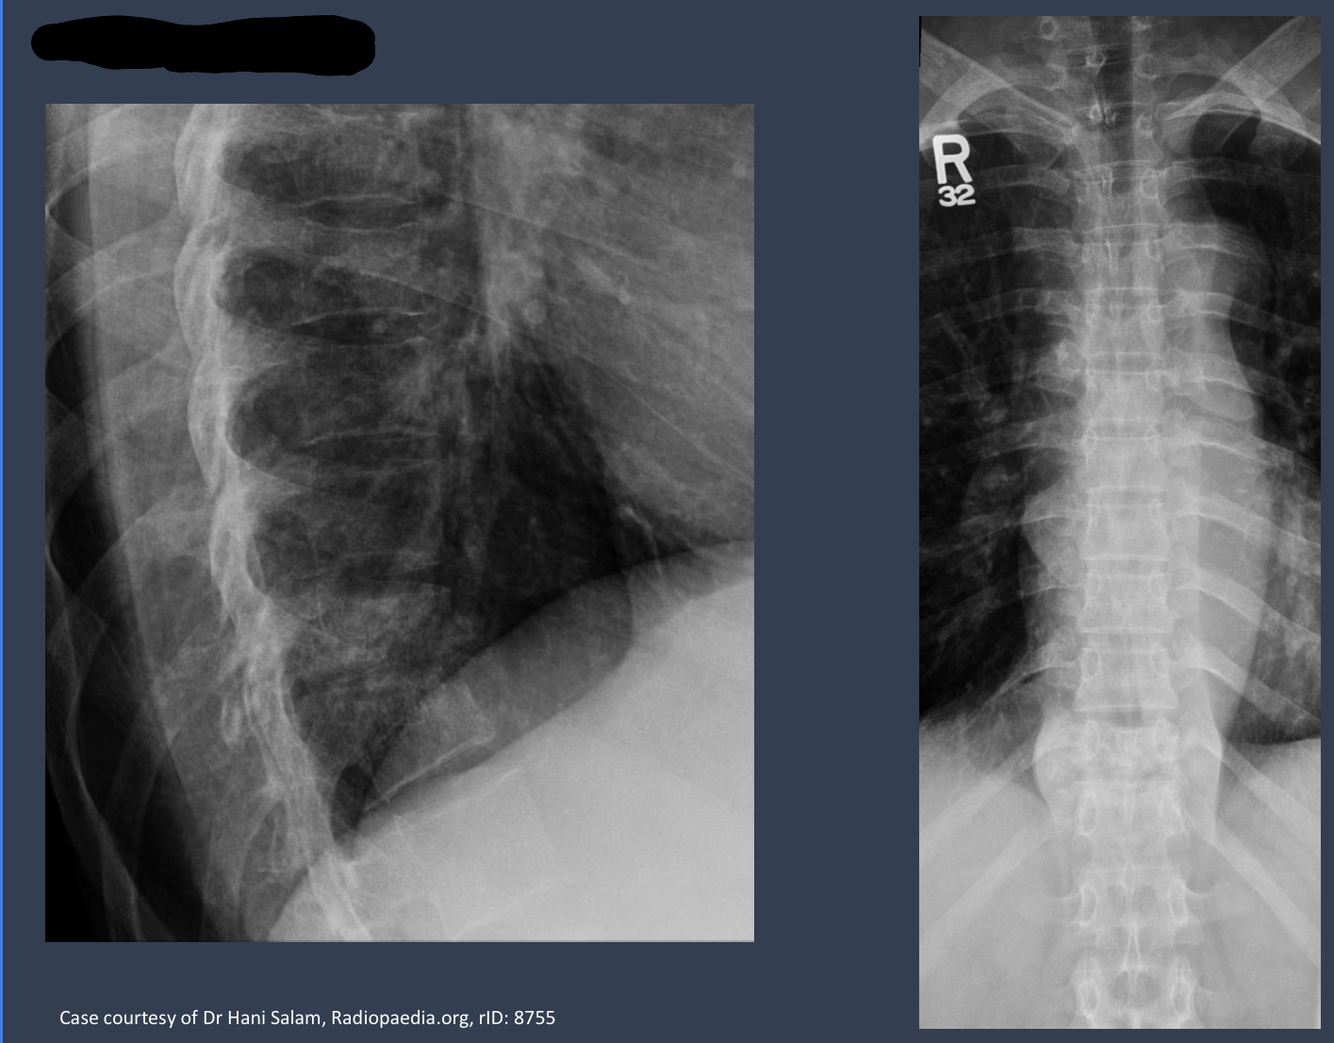

what kind of deformity is this?

what kind of disease is this?

gibbus deformity

a form of structural kyphosis found typically in upper lumbar and lower throacic vertebra where 1+ adjacent vertebrae become wedged. most offten develops in children as a result of spinal TB and is the result of collapse of vertebral bodies.

pott disease

form of TB that occurs outside lungs and seen in vertebra

slower than pyogenic spondylitis. lower thoracic and upper lumbar. begins at endplate. disc space loss is the earliest radiographic sign. lytic destruction 2-5 months.

what condition is this?

describe it

tubercular spondylitis, Pott’s disease

decreased disc space. loss of cervical curve. ??